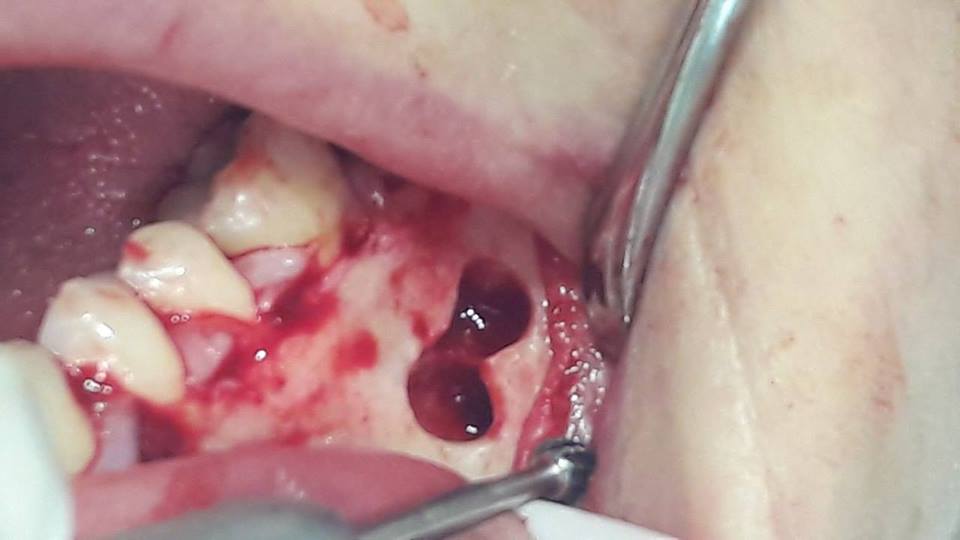

Apicotomy and removal of the cyst of the tooth

Due to unsuccessful endodontic treatment of the first left lower molar, the patient developed a cyst. To preserve the tooth, repeated endodontic treatment was performed, as well as apykotomy (resection of the apex of the tooth root) and the cyst was removed.